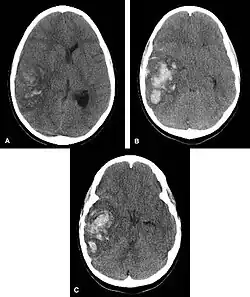

Hemorrhagic neoplasms are more complex, heterogeneous bleeds often with associated edema. These hemorrhages are related to tumor necrosis, vascular invasion and neovascularity. Glioblastomas are the most common primary malignancies to hemorrhage while thyroid, renal cell carcinoma, melanoma, and lung cancer are the most common causes of hemorrhage from metastatic disease.

Diagnosis

Computed tomography (CT scan): A CT scan may be normal if it is done soon after the onset of symptoms. A CT scan is the best test to look for bleeding in or around your brain. In some hospitals, a perfusion CT scan may be done to see where the blood is flowing and not flowing in your brain.